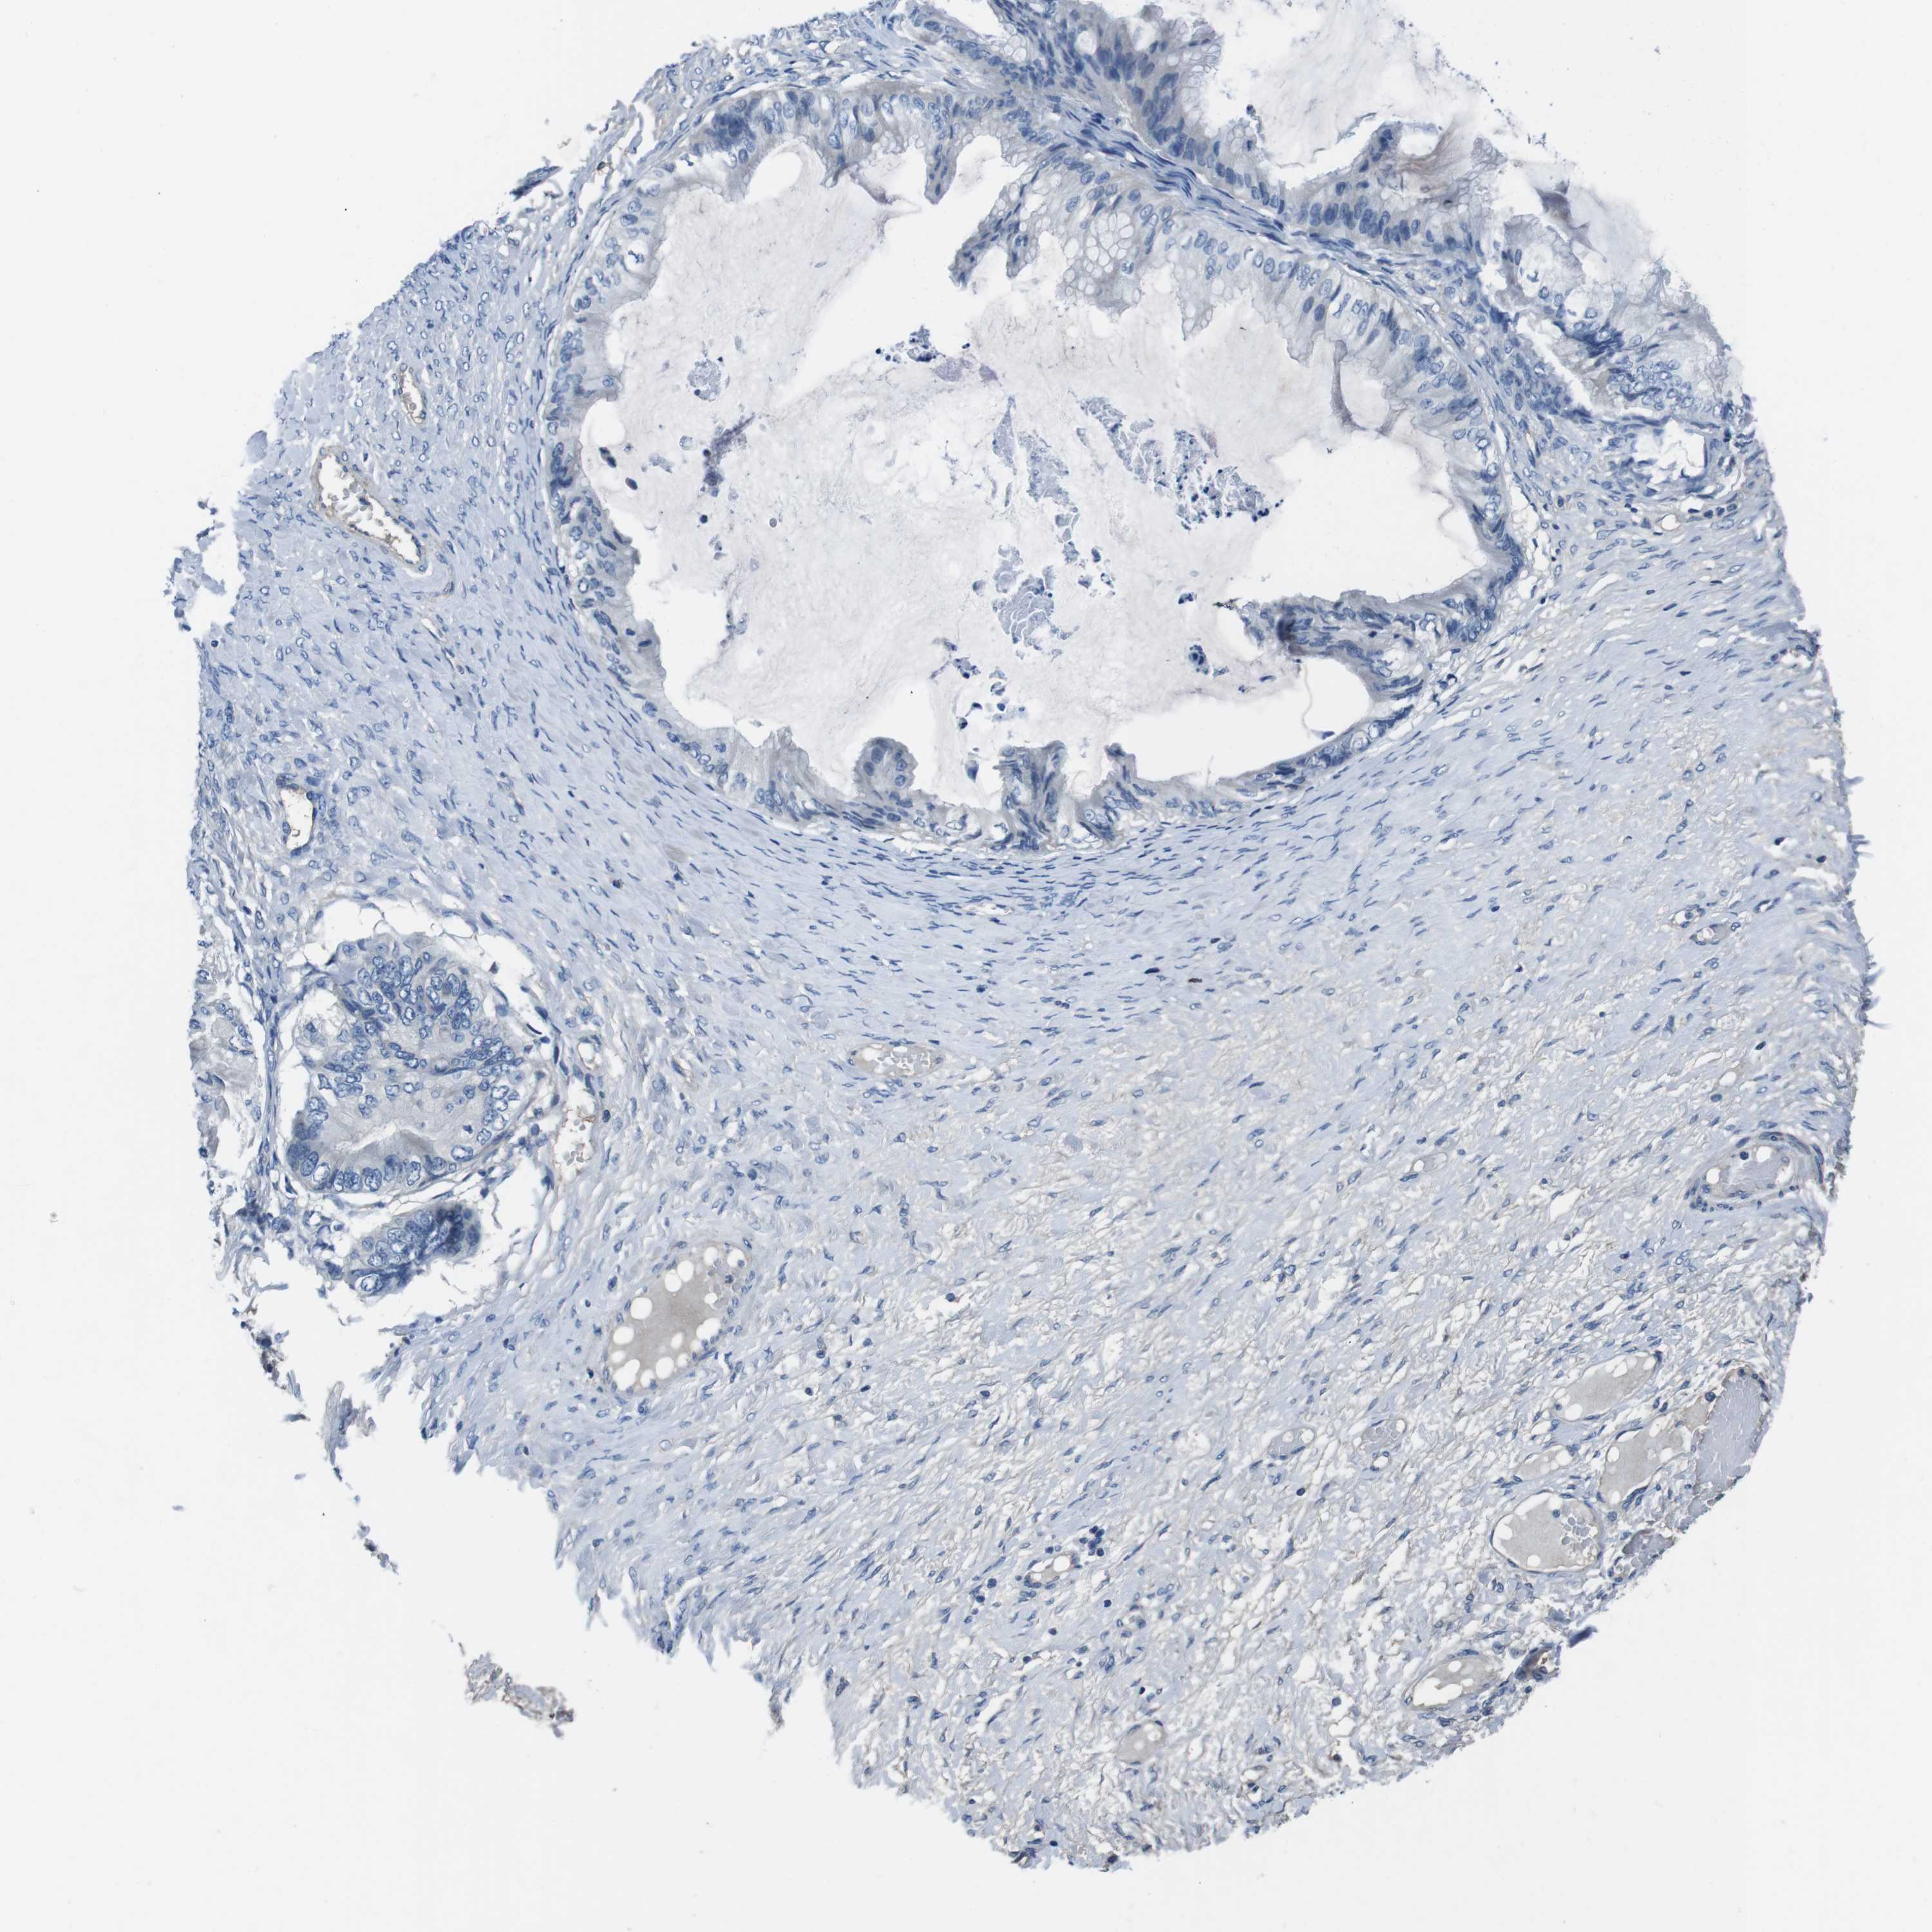

OVARIAN CANCER - Protein expressioni

A mouse-over function shows sample information and annotation data. Click on an image to view it in a full screen mode. Samples can be filtered based on level of antibody staining by selecting one or several of the following categories: high, medium, low and not detected. The assay and annotation is described here.

Note that samples used for immunohistochemistry by the Human Protein Atlas do not correspond to samples in the TCGA dataset.

Antibody stainingi

Antibody staining in the annotated cell types in the current human tissue is reported as not detected, low, medium, or high, based on conventional immunohistochemistry profiling in selected tissues. This score is based on the combination of the staining intensity and fraction of stained cells.

Each image is clickable and will lead to virtual microscopy that enables deeper exploration of all samples and also displays staining intensity scores, fraction scores and subcellular localization as well as patient and tissue information for each sample.

Antibody HPA007845